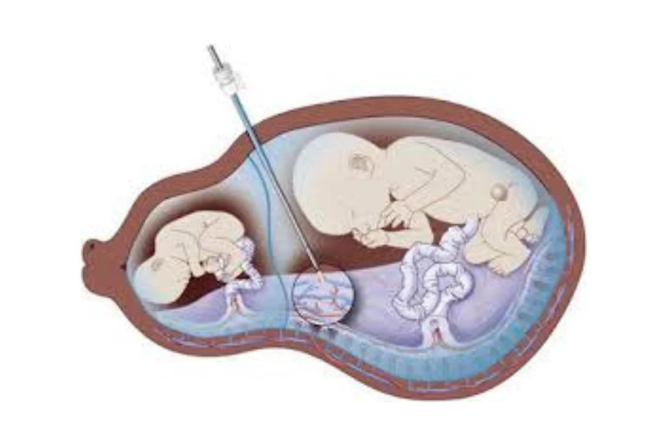

Fetal Interventions

Master minimally invasive procedures. Improve outcomes for complex pregnancies.